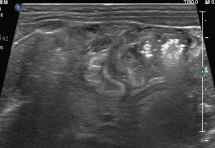

图3:肝区探查,见大量点状高回声相互簇拥着通过门静脉主干,涌入肝内;与此同时,可见肝左叶已散落分布着点、线状高回声,声影不明显。此外,肝周可探及少量不规则液性区。

图4:局部放大,可见大量点状高回声如车流般快速的通过门静脉“主干道”。